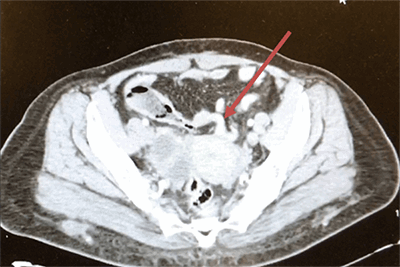

A 48-year-old female with a past medical history of diabetes mellitus presented with abdominal pain. She reported that for the past two days, she had worsening abdominal pain. The pain was localized to her right and left lower quadrants, without radiation and not associated with oral intake. The pain was rated 8/10 and was described as a sharp pain that was constantly present. She also complained of chills and nausea, but no vomiting. She denied diarrhea, any recent falls or injury, and any exposure to ill contacts. On physical exam, her vital signs were pulse 83, respirations 18 and blood pressure 102/59. The abdomen was soft, without rebound or guarding. A positive McBurney’s point and positive obturator sign was noted, with a negative Psoas sign. On admission, her white blood cells were normal at 5.7 but trended up to 18.7 about 14 hours afterwards. Her hemoglobin, and basic biochemistry panel were within normal limits. CT of the abdomen and pelvis with contrast showed findings consistent with acute distal appendicitis. The distal 3 cm of the appendix was thickened to 1.3 cm, fluid-filled and showed adjacent stranding. The segment of distended appendix was seen located within the right anterior paracentral pelvis approximately 3 cm above the umbilicus (Figure 1 and Figure 2). We can also see the sigmoid colon on the right and cecum in the middle of the body (Figure 3).

Figure 1. CT and pelvis showing appendix with fecalith located in the anterior paracentral pelvis

Figure 1. CT abdomen and pelvis showing appendix with fecalith located in the anterior paracentral pelvis